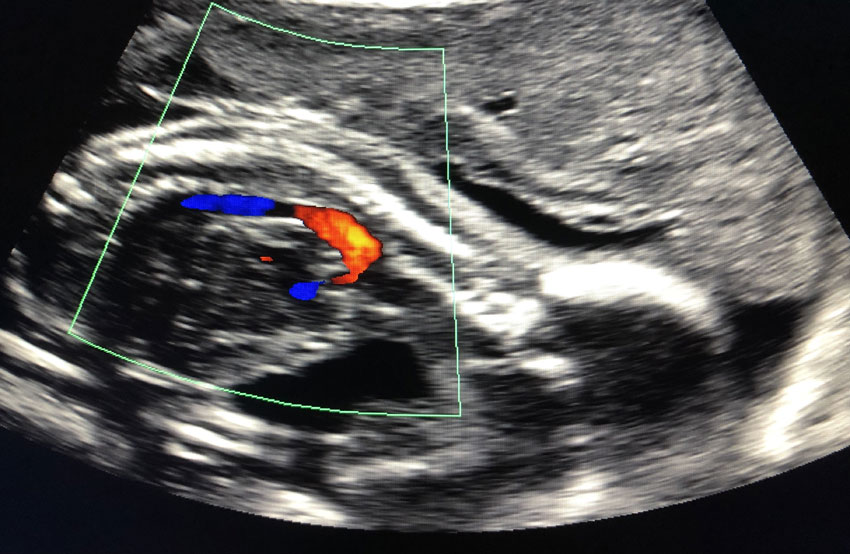

• Fetal Echocardiography: This specialized ultrasound technique focuses on imaging the fetal heart in detail, assessing cardiac structures, function, and blood flow patterns.

• Doppler Ultrasound: Doppler imaging measures blood flow velocity and direction in fetal blood vessels, helping evaluate cardiac function and detect abnormalities.